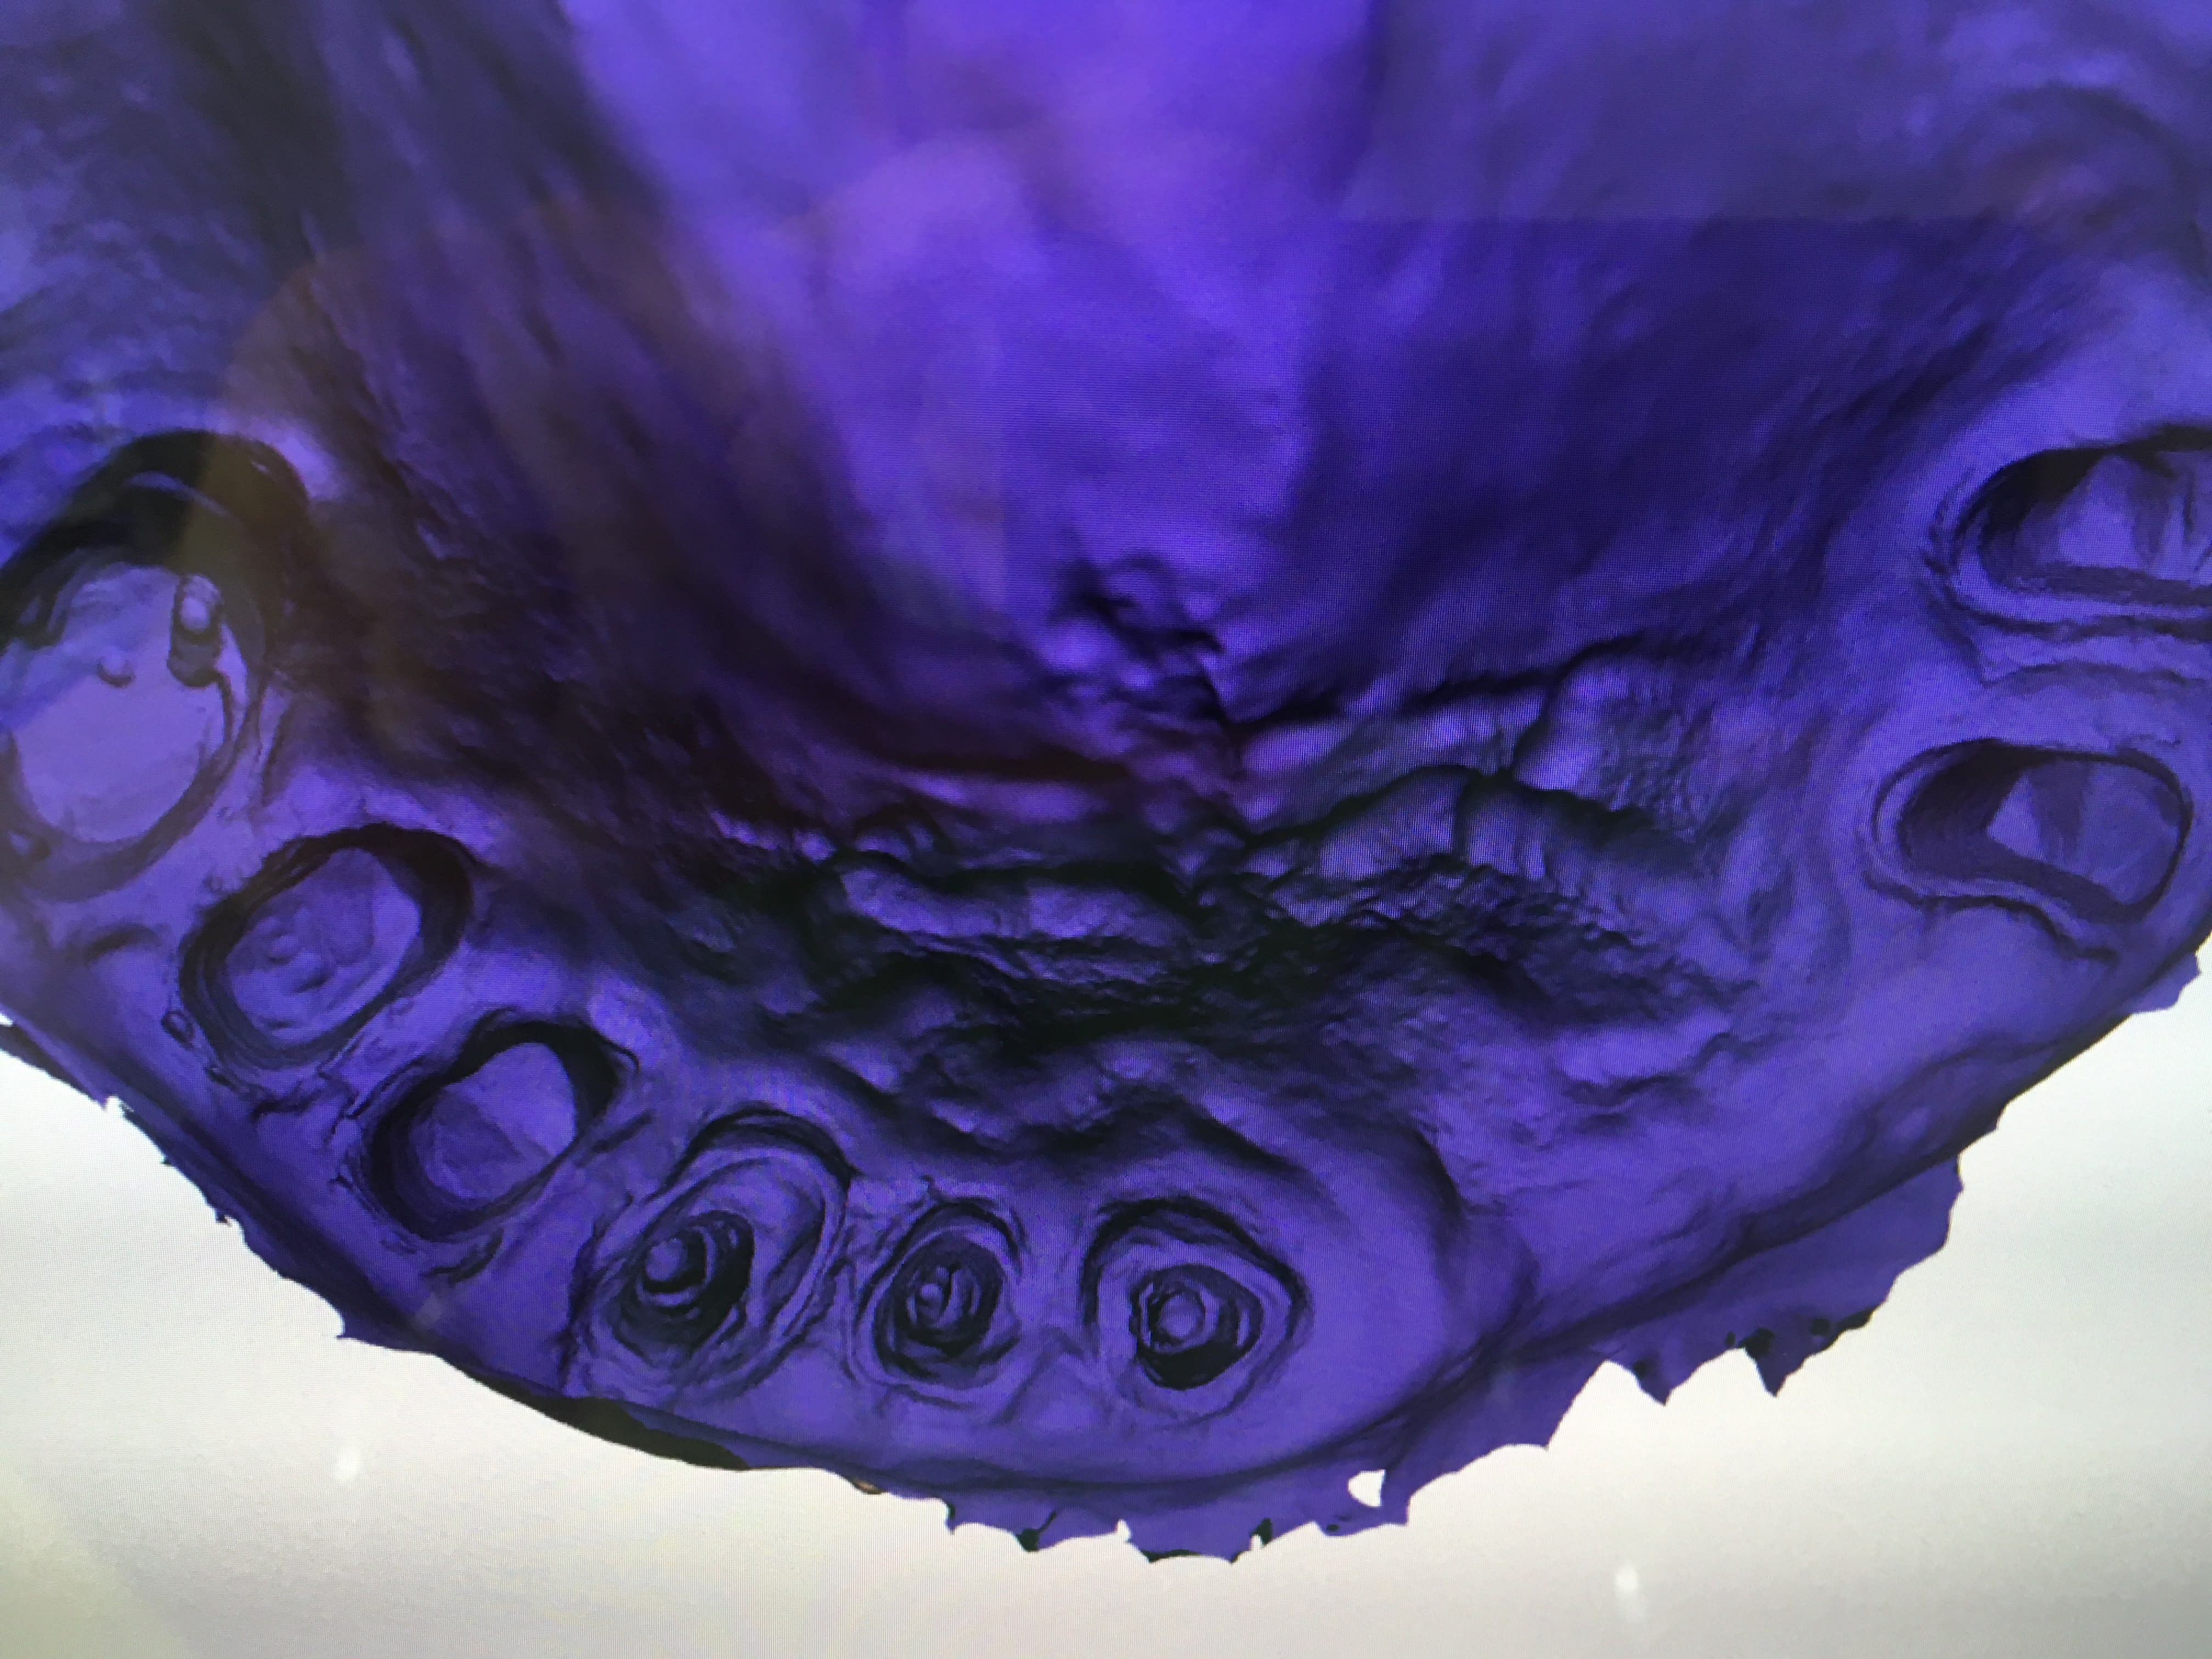

IC ceram 23 + stellite.

Idem que Chicot: Oneshot mais avec un peu plus d’éléments : 3IC, 8 CCM, 1 Stelitte. Aucune retouche autre qu’occlusale. Même Labo, c’est basique mais efficace

Ca te pousse à t'améliorer en fixe : t'évites de toucher la gencive pendant tes tailles : moins ca saigne mieux c'est.